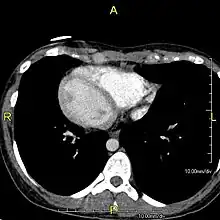

| Situs inversus causes the positions of the heart and lungs to be mirrored. | |

The condition affects all major structures within the thorax and abdomen. Generally, the organs are simply transposed through the sagittal plane. The heart is located on the right side of the thorax, the stomach and spleen on the right side of the abdomen and the liver and gall bladder on the left side. The heart's normal right atrium occurs on the left, and the left atrium is on the right. The lung anatomy is reversed and the left lung has three lobes while the right lung has two lobes. The intestines and other internal structures are also reversed from the normal, and the blood vessels, nerves, and lymphatics are also transposed.

If the heart is swapped to the right side of the thorax, it is known as "situs inversus with dextrocardia" or "situs inversus totalis". If the heart remains on the normal left side of the thorax, a much rarer condition (1 in 2,000,000 of the general population), it is known as "situs inversus with levocardia" or "situs inversus incompletus".

Diagnosis of situs inversus can be made using imaging techniques such as x-ray, ultrasound, CT scan, and magnetic resonance imaging (MRI).[7]